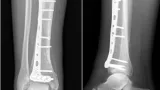

コーレス骨折の患者

11時半に外来に戻り, 転倒後に手首が痛くなった施設入所中の超高齢者を診察.

橈骨遠位端を圧すと痛みがあり, 橈骨遠位端骨折を疑って, X線写真を撮像するようにオーダーしました.

結果は, 予想通りに橈骨遠位端骨折でした.

手の甲側にズレて, 短縮しているコーレス(Colles)骨折と診断.

レントゲン透視室で麻酔後に, 骨折部を元の形に戻すように整復して, ギプス副子固定しました.